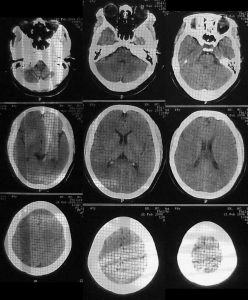

班氏血絲蟲病班氏血絲蟲病

因為日本發動對華戰爭,日人對台灣的血蟲症流行投以較大的注意,而Maxwell與市村兩者互異的說法怕也將成無解的歷史公案。為確保台灣海峽的通過優勢,日本自1935年起擴建澎湖馬公海軍基地並增強其船艦之維修能力。基於軍部要求確保勞動力健康的要求,當時馬公要港部病院海軍軍醫大尉田中重雄,假澎湖馬公基地,檢查澎湖籍工人二百二十九名;發現九十九人具有血絲蟲症臨床症狀,占總受檢人數的43.3%;其中三十七人由末梢血液中檢出血絲蟲,占總受檢人數的16.2%。田中重雄首度證明了這些患者都是班氏血絲蟲症的受害者,這次調查亦是台灣史上第一次以科學檢驗方式確認該種絲蟲的存在。田中且根據患者提供的訊息,主張班氏血絲蟲症不僅僅在馬公高度流行,同時亦流行於澎湖群島的其它島嶼上。一如新竹軍醫中村幸庵發現肺吸蟲症第二宿主般,像田中重雄這類次級軍醫的研究報告,仍須受到當時知識高層—即台北帝國大學醫學部的追認,才能算是通過正確的科學認可程式。1939年正值太平洋戰爭爆發的準備階段,著名的台北帝國大學醫學部寄生蟲學教授橫川定,率領五名該校專技人士小林英一、湯本義香、小坂清石、盧萬德、橫川宗雄(橫川定之子),組成絲蟲症調查團前來澎湖確認田中的報告,並進醫步跨大調查的規模。該調查團在馬公、白砂及西嶼島上四個村落、兩所公學校里檢查2,843人,發現244人感染班氏血絲蟲,感染率為8.6%。